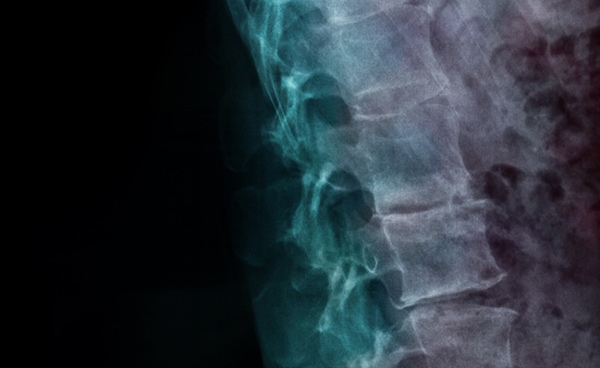

Her Spinal Column

Frida Kahlo’s spine was severely damaged following the streetcar accident in 1925. Her spine never fully healed from the trauma of the accident. In an attempt to manage the chronic pain, Frida had to wear medical corsets for the rest of her life.

In 1946, after being bedridden for four months due to severe spinal pain, Frida agreed to undergo a spinal fusion surgery in New York. The surgery, however, provided little relief. In 1950, her condition worsened and the artist was eventually admitted into the American British Cowdray Hospital in Mexico, where she stayed for nearly a year, undergoing seven operations on her spine.

X-ray of Frida Kahlo’s Spine, 1954, 2023, lightbox installation, Courtesy of the Museo Frida Kahlo Archives. © Banco de México. Fiduciario en el Fideicomiso relative a los museos Diego Rivera y Frida Kahlo.

X-ray of Frida Kahlo’s Spine, 1954, 2023, lightbox installation, Courtesy of the Museo Frida Kahlo Archives. © Banco de México. Fiduciario en el Fideicomiso relative a los museos Diego Rivera y Frida Kahlo. -